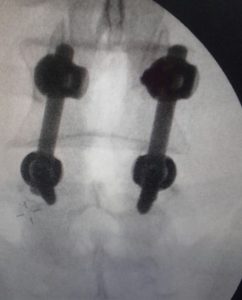

Para lograr una fijación adecuada durante la artrodesis, es habitual recurrir al uso de diversos tipos de implantes quirúrgicos. Entre los más utilizados se encuentran los tornillos, las barras metálicas, las cajas intersomáticas y las placas, etc. Todos estos elementos cumplen una función clave: mantener la correcta alineación de los segmentos vertebrales mientras se produce la fusión ósea, ofreciendo así una estructura sólida y estable.

foto de intervención de artrodesis